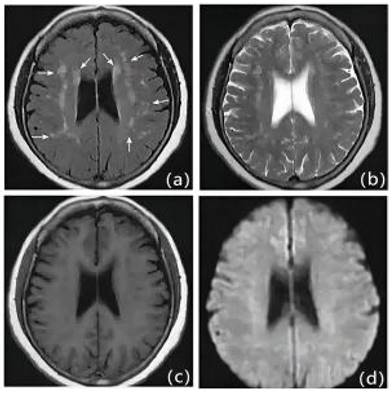

Figure 4

Patients with first-ever IS in ICAS with mild LA: Male, 63 years old, admitted at 15 hours of onset. A: DWI, B: T2WI-FLAIR, C: T1WI, D: MRA. DWI shows multiple lamellar fresh cerebral infarcts in the corpus callosum and left frontal lobe; MRA shows significant stenosis occlusion of the left anterior cerebral artery. T2WI-FLAIR and T1WI show mild cerebral white matter demyelination changes around the bilateral ventricles.